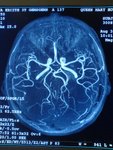

RadioEdric :: 我是白老鼠廿幾號 - 瑪麗醫院新裝之 3T 磁力共振掃瞄器